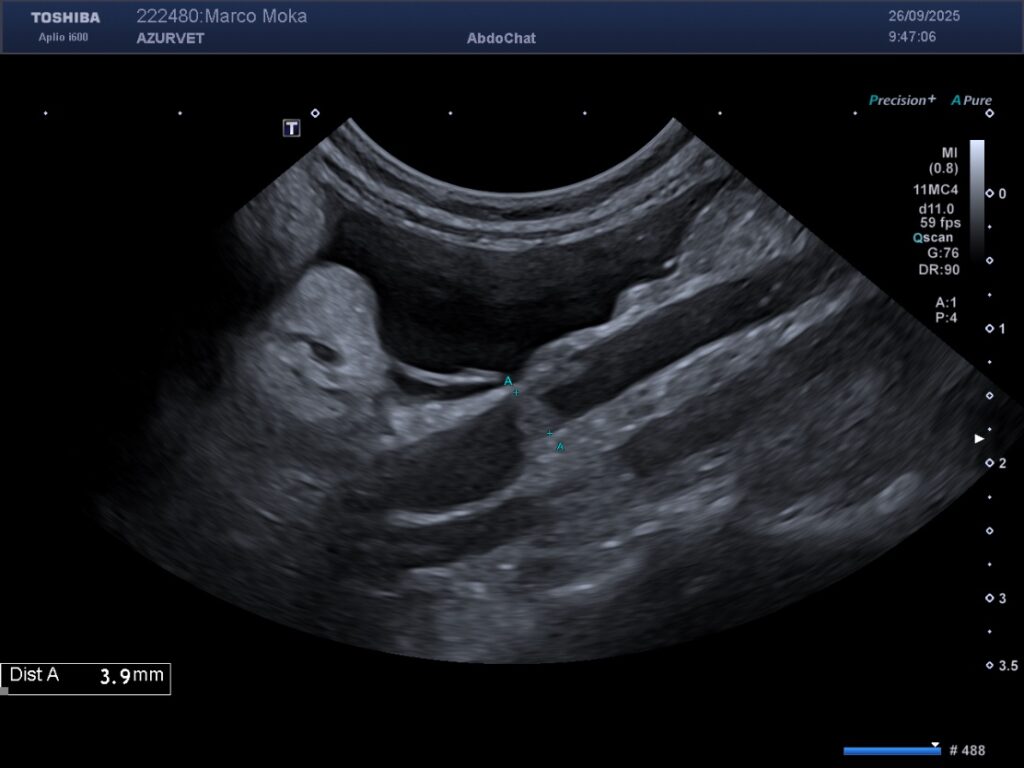

Les lésions muqueuses hyperéchogènes sont typiques d’entéropathie avec perte de protéines chez le chien avec une sensibilité de 76% et une spécificité de 96% dans l’étude de Gaschen et al. Lors de suspicion d’entéropathie chronique chez le chien, la mesure de l’épaisseur seule de l’intestin n’est ni sensible ni spécifique de la présence d’une entéropathie (nombreux faux négatifs). Il convient alors d’apprécier l’aspect de la muqueuse, qui peut présenter soit des « speckles » (= « mouchetures », signe non spécifique ne permettant pas de distinguer le type d’entéropathie), soit des stries hyperéchogènes – figure 1 ci dessous – (corrélé à l’histologie avec une dilatation des glandes lactéales chez le chien, d’après l’étude de Sutherland-Smith et al). Les lymphangiectasies intestinales primitives (ou maladie de Waldmann en médecine humaine), sont caractérisées par des dilatations lymphatiques digestives. Elles entrainent une fuite lymphatique (chyle) dans la lumière intestinale responsable d’une gastro-entéropathie exsudative avec hypoalbuminémie notamment.

Figure 1 : lésions échographiques lors de lymphangiectasie chez un pinscher de 9 ans. Noter l’épaississement pariétal à 5 mm d’une anse jéjunale, la présence de striations et de mouchetures hyperéchogènes dans la couche muqueuse.